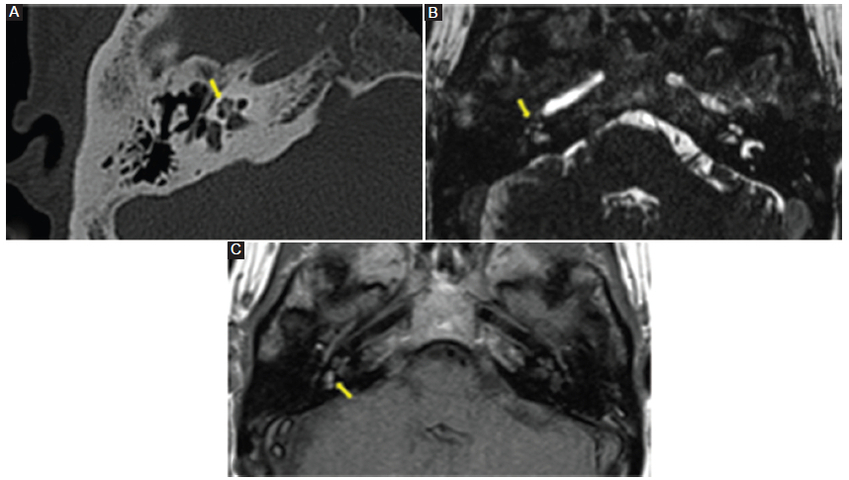

Todos los pacientes con neurinoma intralaberíntico revelaban una baja señal en la secuencia T2 AR, ligera hiperseñal en la secuencia T1 SC y realce poscontraste con márgenes bien definidos (Fig. 3). Tres pacientes con laberintitis inflamatoria (42,5%) mostraron baja señal en las secuencias T2 AR y T1 SC, y 5 pacientes (71%) manifestaban realce con el contraste (Fig. 4), con márgenes menos claros que los pacientes con neurinoma. Los 5 pacientes con laberintitis osificante presentaron baja señal en la secuencia T2 AR, y 2 pacientes (40%) tenían hiperseñal en la secuencia T1 SC (Fig. 5). Solo en 3 pacientes con laberintitis osificante se realizó secuencia con contraste, y 2 de ellos mostraron realce. Los 3 pacientes con hemorragia evidenciaron una señal alta en la secuencia sin contraste (Fig. 6) y 2 (66,7%) presentaron refuerzo poscontraste (Tabla 2).

La RM puede ayudar al diagnóstico con la secuencia T2 AR, mostrando una señal intermedia, baja o ausente dependiendo de la gravedad de la enfermedad. Puede evidenciarse hiperintensidad en la secuencia T1 SC y ligero realce con el contraste. Este último puede estar presente tanto en los casos de laberintitis membranosa, una etapa precursora de la laberintitis osificante, como en la etapa osificante misma.

De cualquier manera, el método de elección para su diagnóstico es la TC del hueso temporal en ventana ósea, la cual puede mostrar una hiperdensidad sutil del laberinto membranoso en los casos más leves y una osificación completa del laberinto en los casos más graves.

Acorde con estos hallazgos, en nuestra muestra, el 100% de los pacientes con esta patología presentaron baja señal en la secuencia T2 AR2,9,10,11.